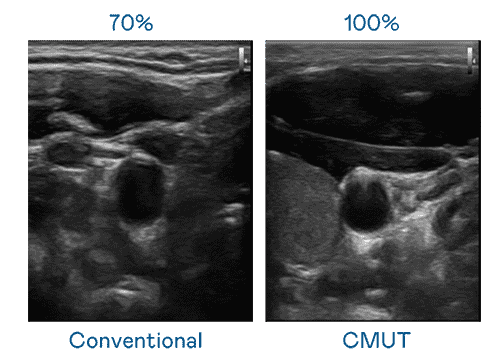

CMUT 技术是一种用电容式微机电元件来产生超音波讯号的技术。。与传统 PZT 压电式技术相比,,CMUT 频宽增加 30%,,,,更宽频的超音波讯号让影像解析度大幅提升,,,是实现高影像品质医疗超音波扫描、、促进精准医疗发展的关键技术。。。

大频宽带来超清晰影像

超音波影像的解析度高低,,,首先取决于探头能发出的讯号频宽。。。MG电玩 CMUT 可提供高清晰的超音波讯号,,,,提供高频宽、、、高灵敏度、、、、影像纹理细节更高的超音波影像,,,,协助医护人员缩短影像判读时间及利用精准的医疗影像进行诊断。。。。